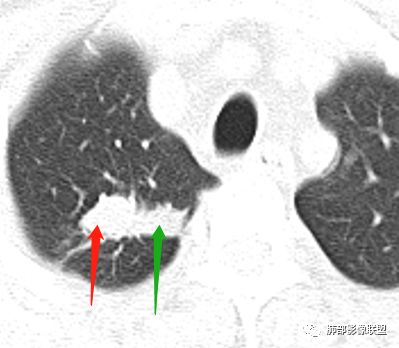

右肺上叶病灶两部分

纵隔窗提示内侧部分密度不够实

边缘平直、凹陷为主,部分膨隆

内部小点状影提示可能支气管腔内粘液栓

左肺尖及右肺病灶附近见小斑点,边界尚清

这些是否是边界清楚GGO?

南边:2、不踏实的地方:GGO是不是容积效应所致?如果薄层,边界清楚GGO,就考虑继发瘢痕癌

因此我们需要的是:薄层、重建,看GGO边缘、看整体形态